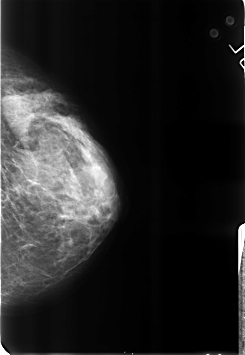

B_3184_1.LEFT_CC

LEFT_CC LINES 4608 PIXELS_PER_LINE 3184 BITS_PER_PIXEL 12 RESOLUTION 50 NON_OVERLAY

LEFT_MLO LINES 4592 PIXELS_PER_LINE 3104 BITS_PER_PIXEL 12 RESOLUTION 50 NON_OVERLAY